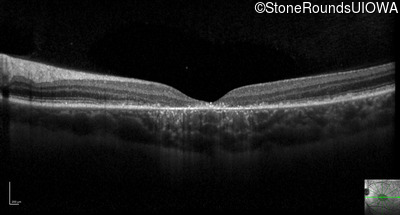

Optical Coherence Tomography - Right - 20/160 -1 sc

Exemplar / OCT Stack

OCT Stack